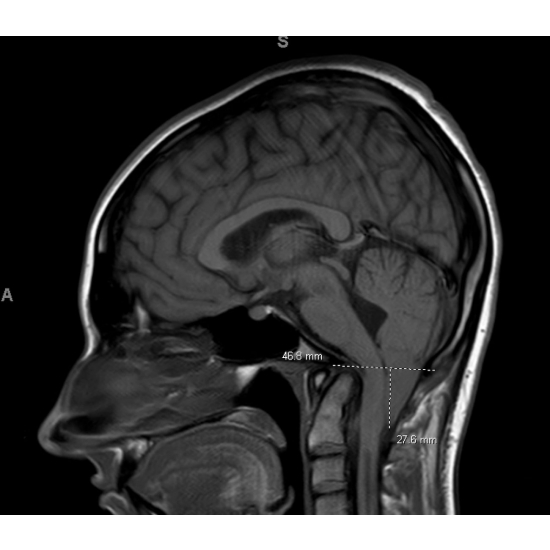

MRI brain without contrast: Redemonstration of malformation with the obex 28 mm below the level of the foramen magnum. Elongation of the fourth ventricle. Case Photo #6